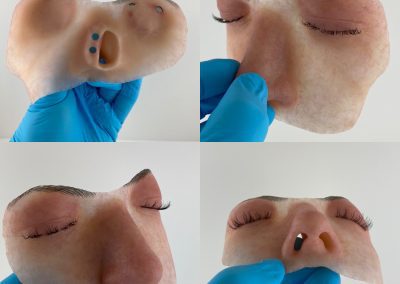

Histology is the study of the different tissues of the human body at the microscopic level. Understanding the structures of the human body from the macroscopic (Anatomy) to the microscopic (Histology) levels will aid in anaplastology treatment planning.

Cancer, birth differences and traumatic incidences, the most common reasons patients seek the care of clinical anaplastologists, will impact different tissues in the body: bone, skin, muscle. Having a microscopic understanding of these tissues could influence patient care.